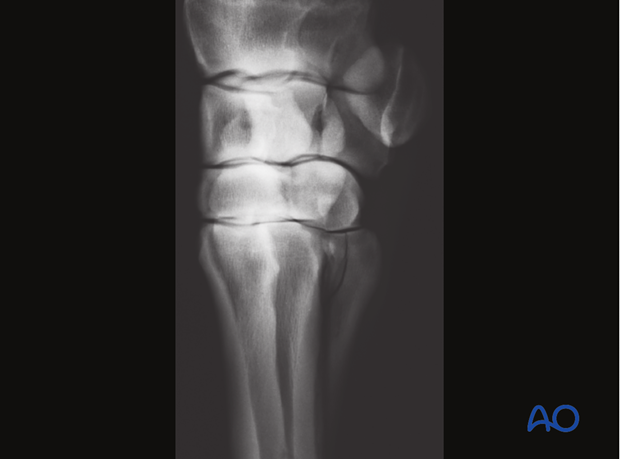

Screws may engage only the splint bone (left) or include the near cortex of the third metacarpal/metatarsal bone (right).

The fusion of the splint bone with the third metacarpal/metatarsal bone results in joint stability; however, this is not ideal from a physiological standpoint because it eliminates normal micro-movement within the joint and between the splint bone and the third metacarpal/metatarsal bone.

Therefore, whenever possible the screws should only engage the fractured bone.

Occasionally, one cannot achieve sufficient stability with screws placed in the splint bones only. In such cases inclusion of the palmaro/plantaro-lateral/medial cortex of the third metacarpal/metatarsal bone in the fixation should be considered.

It must be kept in mind, that this eliminates normal micro movement within the joint and between the splint bone and the third metacarpal/metatarsal bone.